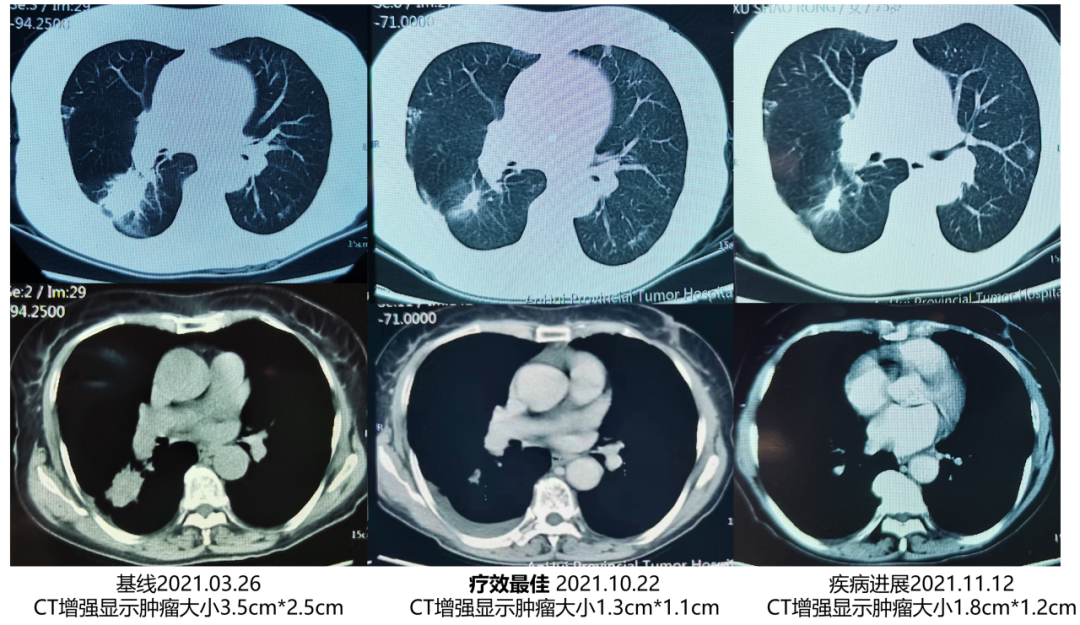

2021年3月26日:增强CT示肿瘤大小3.5cm*2.5cm。

参加临床试验,2021年3月底开始口服特泊替尼,5月底CT示肿瘤大小1.4cm*1.3cm,11月12日为1.8cm*1.2cm,病灶较前变大伴纵隔右肺门稍大淋巴结,疾病进展出组。

一线治疗前后影像对比